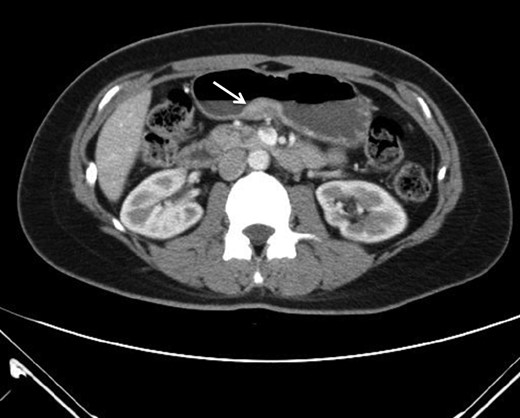

This is a 38-year-old female without any underline disease who came to our out-patient department due to a 2-month history of intermittent abdominal fullness and distension sensations. At first, she visited our gastroenterologist where medications promoting bowel motilities were prescribed but in vain. To further assess her condition, endoscopic ultrasonography was arranged which revealed a hypoechoic tumor with a diameter of 21.3 mm arising from the fourth layer of gastric wall. (Figs 1 and 2) An endoscopic biopsy was performed but reported negative findings due to failure in acquiring submucosal specimens on that biopsy. Based on epidemiology, gastrointestinal stromal tumor was suspected. Computed tomography was then arranged (Fig. 3) which revealed a submucosal tumor with heterogenous enhancement posterior wall of gastric antrum. No other lesion was found during that examination. Under such findings, she was then referred to a gastrointestinal surgeon for further surgical intervention.

Heterotopic pancreas is a congenital anomaly with a reported prevalence of 0.5–13.7%. The most common locations are the upper gastrointestinal tract such as the stomach, duodenum and proximal jejunum. The less common sites are the esophagus, ileum and biliary tree. The diagnosis of heterotopic pancreas prior to surgery is difficult as it is generally asymptomatic. Besides, it also shares common features of the submucosal lesion under endoscopic (Fig. 4) or computed tomography examination. Although so, pathological changes similar to that of a normal pancreas (acute or chronic pancreatitis, cystic degeneration, malignant changes) are possible [4, 5]. Other than that, symptoms due to its anatomical position or tenderness resulting from the secretion of hormones and enzymes could all necessitate surgical interventions. By reviewing works of literature, we are able to gather some clues which might help us differentiate HP from other lesions before a treatment strategy is modulated. On conservative evaluations, a study conducted by Li et al. suggested that for masses <3 cm, a long diameter to short diameter ratio (LD/SD) greater than 1.29, enhancement value of >27.50 HU, enhancement ratio to pancreas of >0.72 are critical features [6]. Besides that, another study by Maryam et al. describes the MR imaging appearance of heterotopic pancreas mimics orthotopic pancreas. Characteristics of high signal intensity of the pancreas at T1-weighted imaging is useful for differentiation. Other than that, T2-weighted and MR cholangiopancreatographic images could help identify rudimentary or dilated ducts in the heterotopic pancreas to aid in differentiations [7]. Although endoscopic findings of central dimpling or umbilication which corresponds to an opening of a duct are the typical endoscopic finding for heterotopic pancreas, Haetaek et al. reported that it is seen in only 1/3 of cases. However, by using magnifying endoscopy with narrow band imaging, they can identify microscopic opening in more than 80% of lesions without a macroscopic opening, which suggests the possible usefulness of this method in predicting the diagnosis of heterotopic pancreas [8]. As for intervention approaches, endoscopic ultrasonographic fine needle aspiration (EUS-FNA) was reported to have a high sensitivity but somewhat limited diagnostic accuracy due to the limited quantity of tissue sample. A new technique of incorporating endoscopic submucosal dissection known as submucosal endoscopy with mucosal flap (SEMF) which could directly visualize the tumor or perform core biopsies has reported specific features of heterotopic pancreas as ‘yellow, cloudy, and soft with small nodule appearance similar to the pancreas.’ This endoscopic visualized features (EVF) could provide clues for the diagnosis of heterotopic pancreas. If uncertain, this technique could also provide the convenience of core biopsy samples for diagnosis prior to surgeries [3].